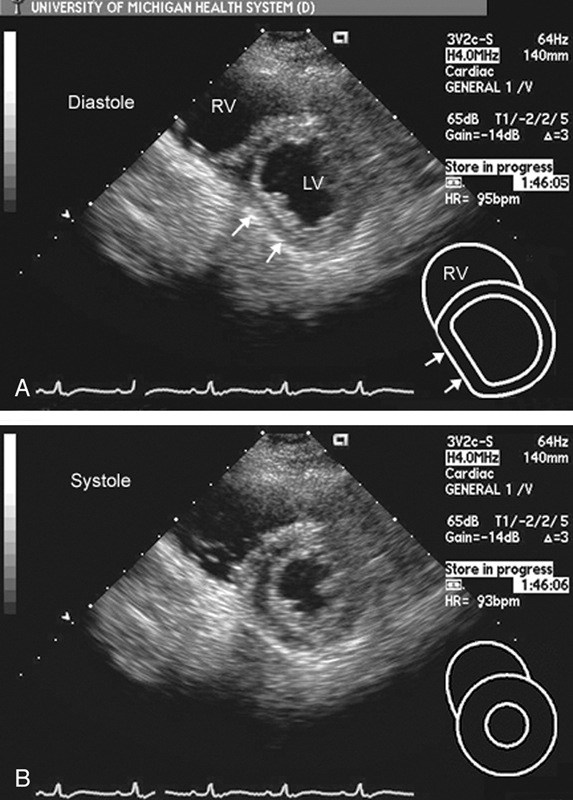

فحوصات تشخيصية لبعض امراض القلب والشرايين التاجية